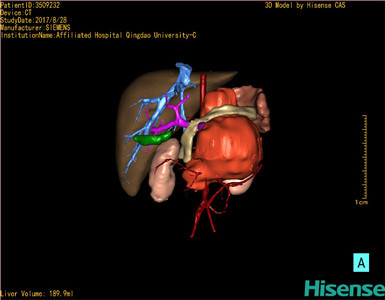

CT结果输入海信CAS系统后行3D重建及手术规划后,于2017-8-29全麻下行“腹膜后畸胎瘤切除术+肠系膜上动脉吻合术”手术治疗:

术前三维重建及手术方案设计:

将0.625mm双源薄层CT资料的静脉期和动脉期Dicom格式文件导入海信CAS系统。

通过调节窗宽窗位调整CT序号,对肿瘤,肝实质,胆囊,下腔静脉,肿瘤,肝动脉、门静脉及肝静脉等进行三维重建;系统自动计算肿瘤体积和肝脏体积。

模拟手术操作,自动计算切除肿瘤体积。肝脏体积为453.7ml,通过比对2-3岁正常肝脏体积为475.97±99.7ml,通过术前模拟手术,精准判断切除后剩余肝脏体积能耐受,避免肝衰竭发生。

术前三维重建:

重建图片